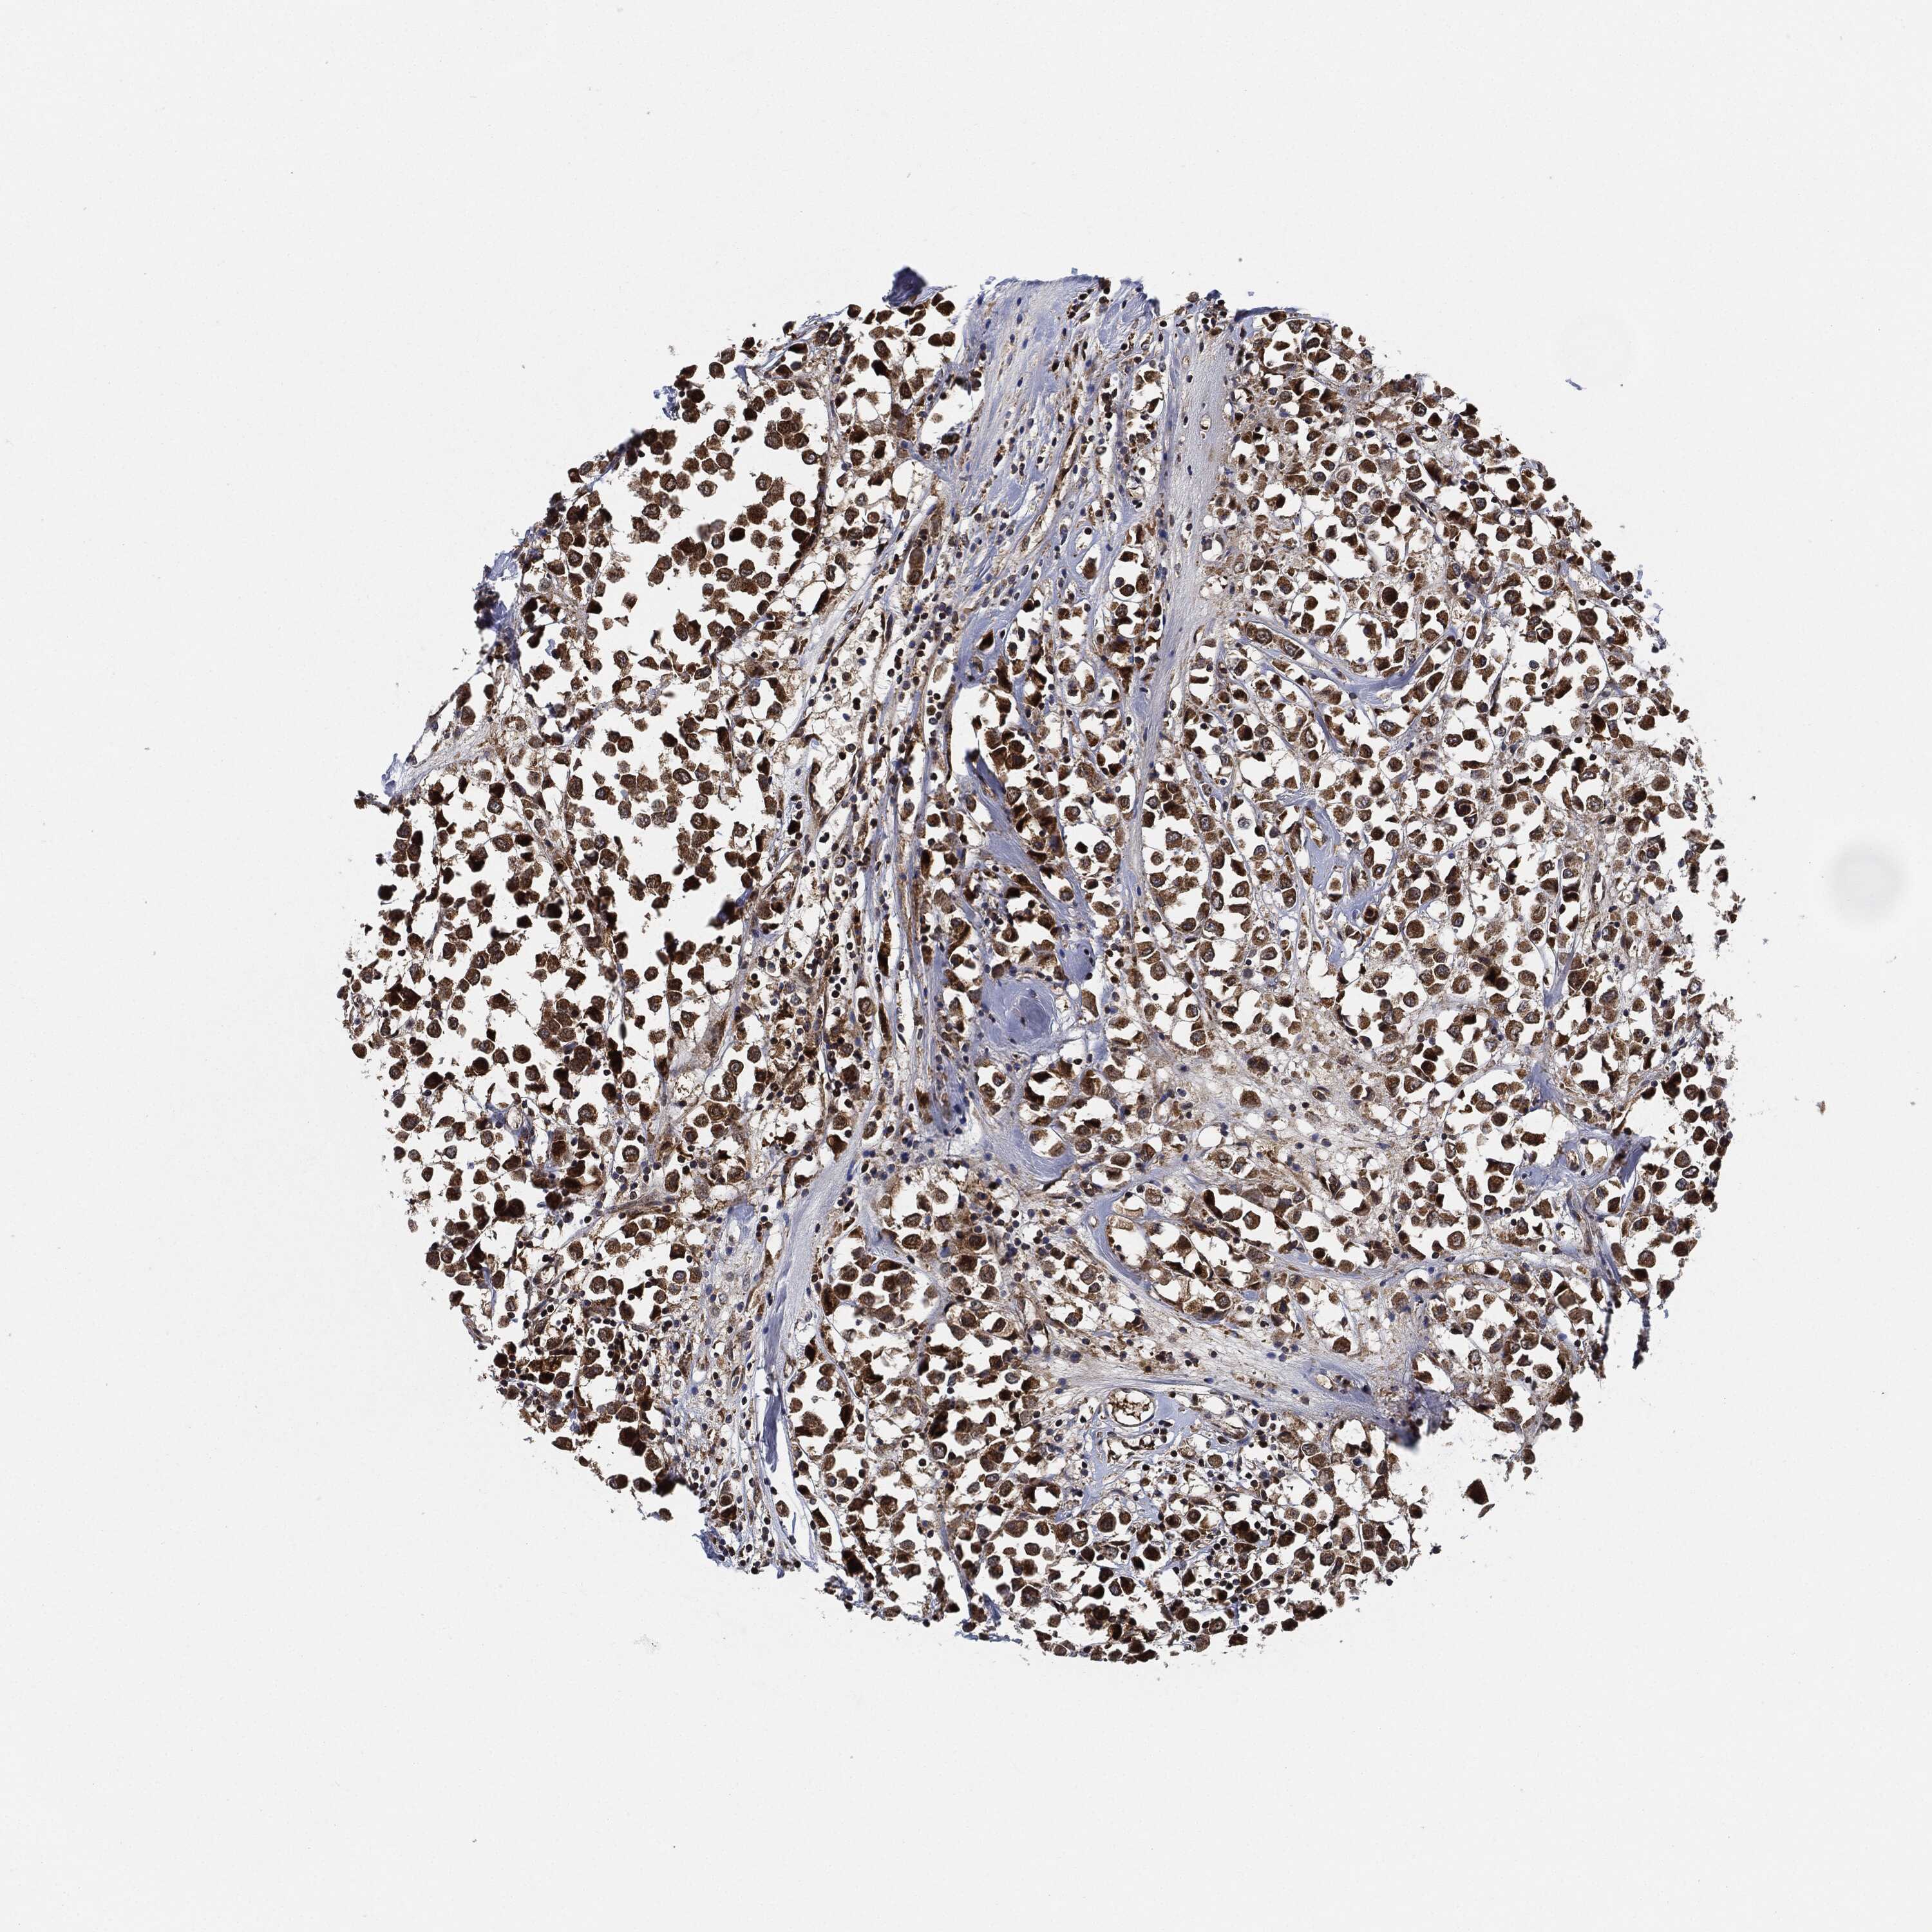

BRCA TCGA BRCA VALIDATION PROTEIN EXPRESSION

ANTIBODIES

AND

VALIDATION